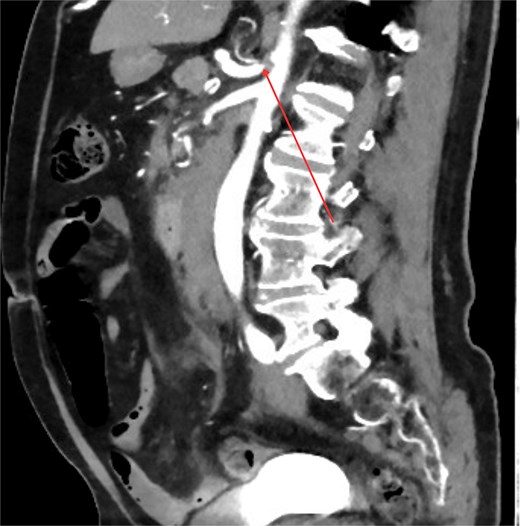

Three days post-discharge, the patient re-presented to the hospital with persistent vomiting and oral intolerance, consistent with gastric outlet obstruction. His repeat Hb is also stable with 119 and normal INR. The repeat CT was performed, which revealed extrinsic compression of the duodenum by the organizing hematoma and duodenitis noted. He was transferred to a tertiary center for further management. Nasogastric tube was inserted for gastric decompression. The endoscopy was performed the next day which showed normal endoscopic finding and naso-jejunostomy tube was placed for feeding. Within 3 days of admission, his Hb has slowly down trending to 99 and therefore, CT multiphase scan was arranged. Crucially, the CT scan identified tight stenosis of the celiac trunk (Fig. 2) and a distinct aneurysm within the pancreaticoduodenal artery arcade.

Sagittal contrast-enhanced CT image demonstrating significant stenosis at the origin of the celiac axis. The site of the narrowing is marked by arrow.